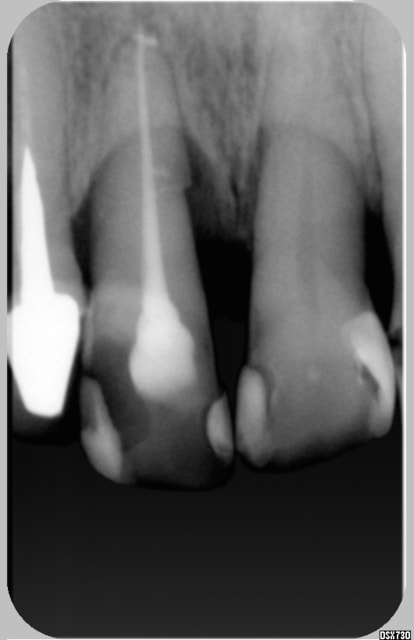

Est ce vraiment unr fracture?

Je vous joint une radio prise en oct 98, la 11 est mobile sans grande sensibilté au froid, suppra profonde.

J'ai soulagé l'occlusion, et surfacage , tout est rentré dans l'ordre

elle revient en 09/2004 apres un épisiode douloureux avec abcés, j'ai éléimine d'emblée un problême paro, et plus de sensibilité

j'ai traité la dent, voir la deuxiéme radio

Un beau canal latéral

depuis génée devant au niveau collet gingival, j'ai du cureté l'exces de pate, la dent n'a plus de mobilité, et les douleurs ont disparues

jeff2 ton cas pour moi c'est pas un canal lateral au depart c'est une felure car sur la derniére image il me semble qu'il y a un decrochement en mesial qui est apparu et qui traduit le deplacement Non???. D'ailleurs le parodonte environnant n'est pas stabilisé.......enfin me semble-t -il

Jeff2, ton cas ne correspond pas au mien regarde bien l'image du canal...

canal lat ou fracture? la derniere radio ne Jeff2 ne m'a pas encore convaincu...mais c'est vrai que l'endo est tres belle...